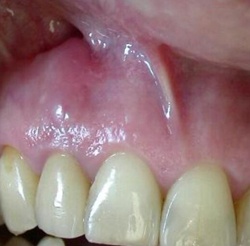

La mise en place d'un implant au niveau d'une crête osseuse se situant dans le secteur antérieur doit tenir compte de 2 facteurs essentiels. Le premier : pour que la papille inter-dentaire se régénère, il faut que la plate-forme de l'implant se trouve à une distance d'environ 3mm de la jonction amélo-cémentaire des dents adjacentes. Le deuxième : lorsque un implant est mis dans une crête, il doit être recouvert en vestibulaire et en palatin d'une couche osseuse d'au moins 2 mm.